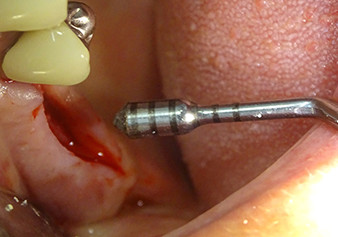

The Schneiderian membrane is carefully detached with the Z25P instrument (phase 1)

Fig.3: Following marking of the implant position and initial expansion of the bed, the Schneiderian membrane is carefully detached with the Z25P instrument (phase 1).